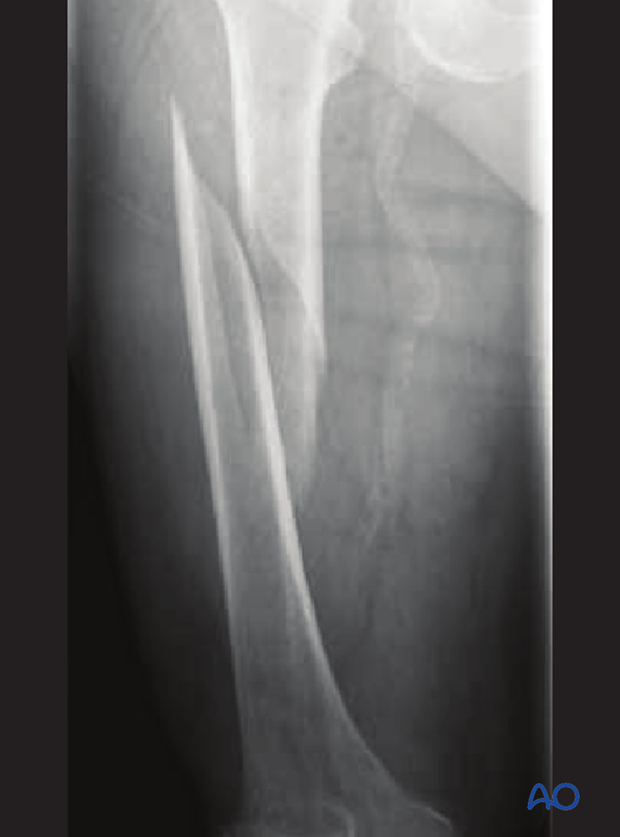

Spiral/Torsion Fracture

The break coils around the bone - common in femur fractures